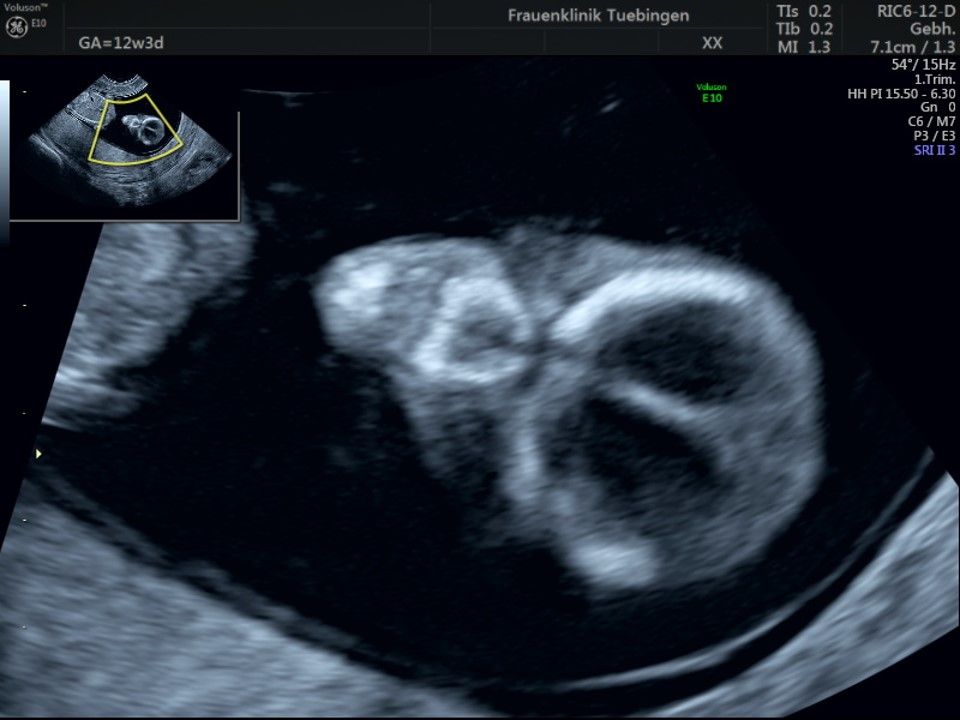

Bauchwanddefekt